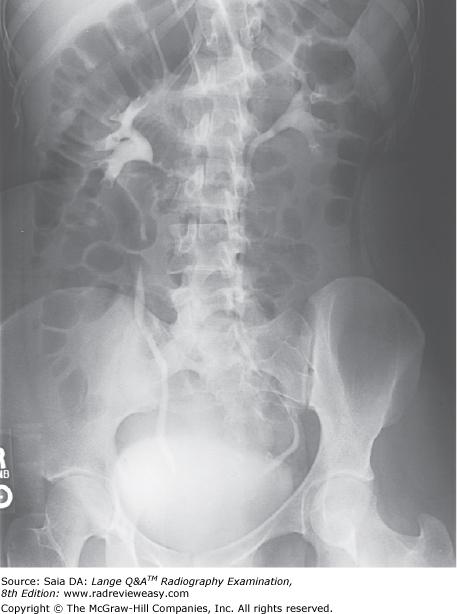

The ileocecal valve normally is located in which of the following body regions?

A Right iliac

B Left iliac

C Right lumbar

D Hypogastric

-The abdomen is divided into nine regions. The upper lateral regions are the left and right hypochondriac, with the epigastric separating them. The middle lateral regions are the left and right lumbar, with the umbilical region between them. The lower lateral regions are the left and right iliac, with the hypogastric region between them. The ileocecal valve, cecum, and appendix (if present) are located in the lower right abdomen—therefore, the right iliac region